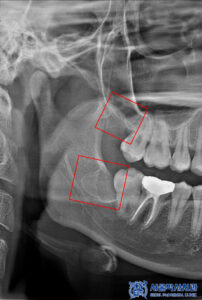

먼저 충치가 매우 깊었던

왼쪽 위 큰 어금니는

충치로 인해 치아가 파절되어 있는

상황이었습니다.

또한 씹는면 주변으로

치석이 쌓여있는 것으로 보아

관리가 잘 안되고 있는것으로

볼 수 있었습니다.

해당 부위는 신경치료를 진행하여

깊은 충치로 인한 치아 내부의

감염을 제거하고 치아의 기능을

회복할 수 있도록 했습니다.

또한 치아 뿌리까지 노출된 상태였고

신경 오염이 많이 된 상태여서

자연치아를 살리기에 많은 노력이

필요한 상황이었습니다.